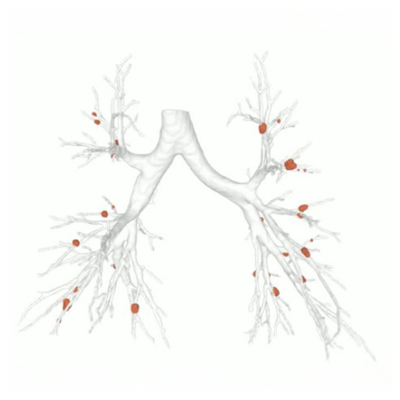

Mucus plugs

Quantitative assessment

AI-based quantitative analysis in evaluating the efficacy of Bronchial Rheoplasty

Chronic Bronchitis(CB) is characterized by excessive airway mucus production and is often associated with significant airway obstruction from mucus plugs. Bronchial Rheoplasty(BR) treatment is expected to address mucosal inflammation and hypersecretion.

By utilizing LungQ® MP and bronchi analysis to gain longitudinal insights, the treatment’s efficacy was quantitatively demonstrated through CT imaging: CB patients experienced a significant reduction in mucus plugs in 6 months following BR. This objective improvement directly aligns with patient-reported symptom relief, confirming the therapeutic mechanism.